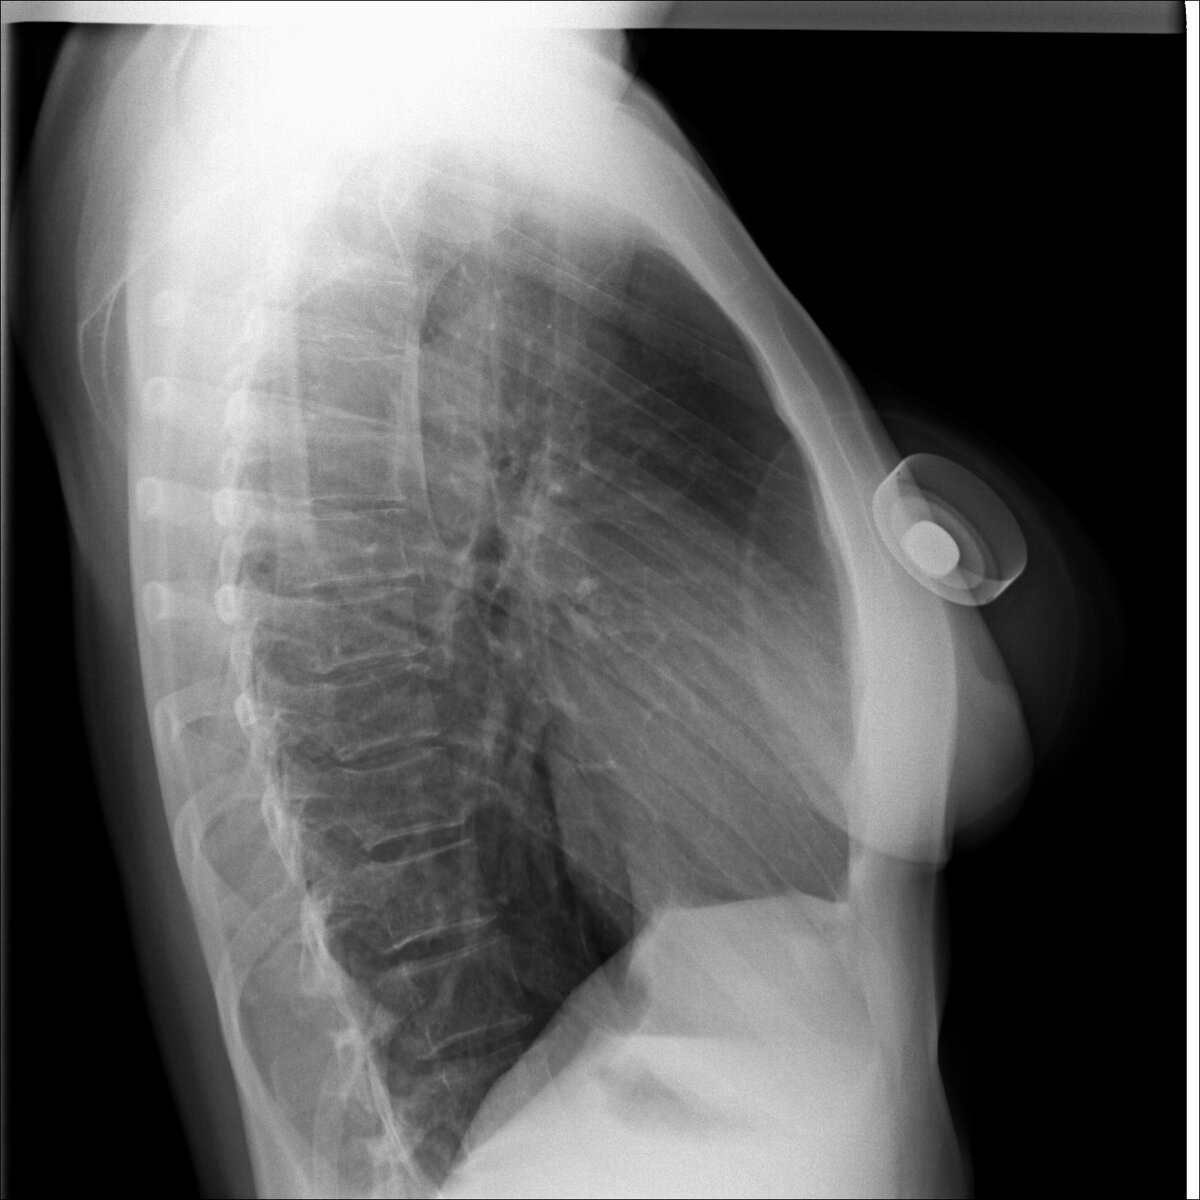

In the second picture a similar subject but of a different design. Location in the right axillary region.

На втором снимке аналогичный предмет, но другой конструкции. Расположение в правой подмышечной области.

These are the so-called PowerPorts for the introduction of drugs into the patient.

Это так называемые порты для введения лекарственных средств в организм пациента.

A young doctor or medical student may be confused by this shadow. But there is nothing wrong with it. PowerPorts are used when the patient is on an outpatient basis (they are not kept permanently at the hospital), but this necessitates the constant administration of drugs intravenously.

Молодого врача или студента медика может смутить данная тень. Но ничего страшного в ней нет. PowerPorts используются тогда, когда больной находится на амбулаторном лечении (ненаходится постоянно в стациаонаре), но при этом возникает необходимость постоянного введения лекарственных средств внутривенно.

Most often, such devices are used in the treatment of cancer and the patient undergoing chemotherapy.

Чаще всего такие устройства используются при лечении рака и прохождении пациентом химиотерапии.

PowerPort is installed under the skin and injected into one of the vessels. Most often in the subclavian vein.

Устанавливается PowerPort под кожу и вводится в один из сосудов. Чаще всего в подключичную вену.